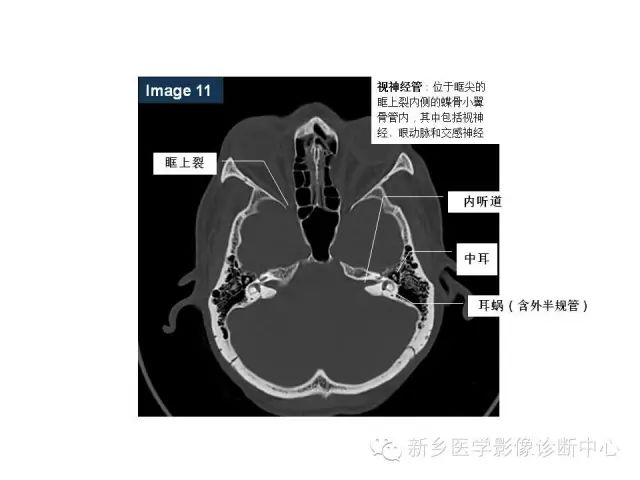

鼻咽部的详细解剖(含各个孔道)

来源:新乡医学影像诊断中心